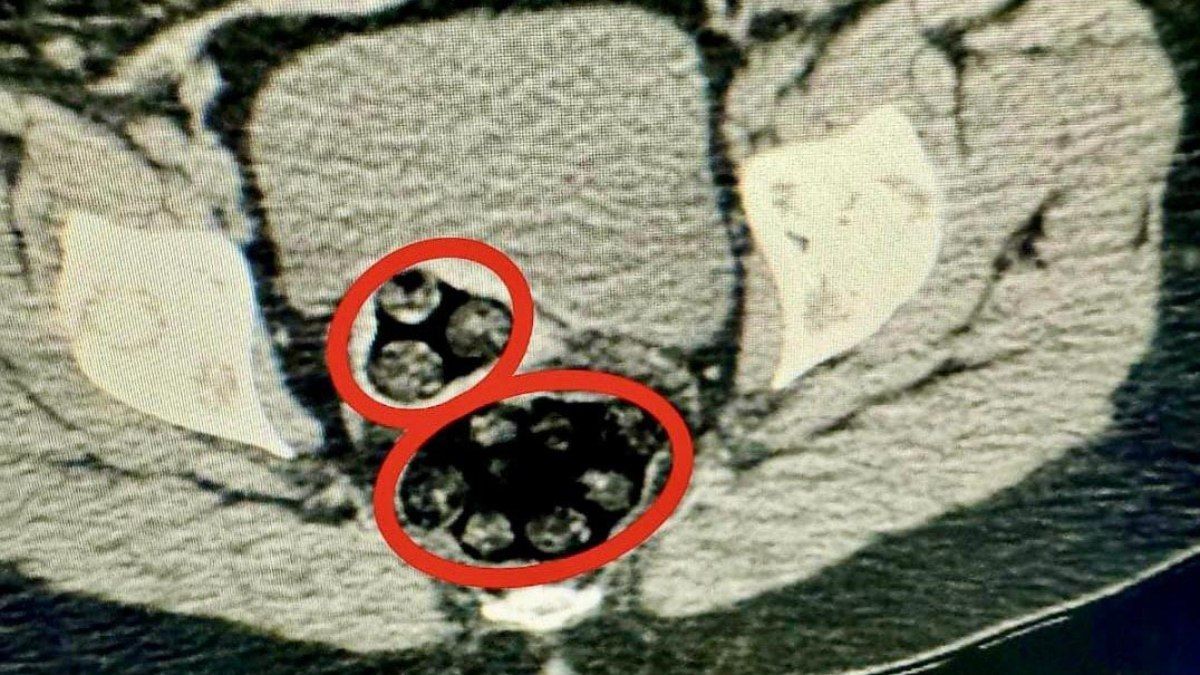

Kars Harakani Devlet Hastanesi’ne götürülen Yenkejeh’in çekilen röntgeninde, makatında uyuşturucu tespit edildi.

Doğal yolla kadının makatından 94 parça halinde toplam 550,93 gram metamfetamin çıkarıldı.